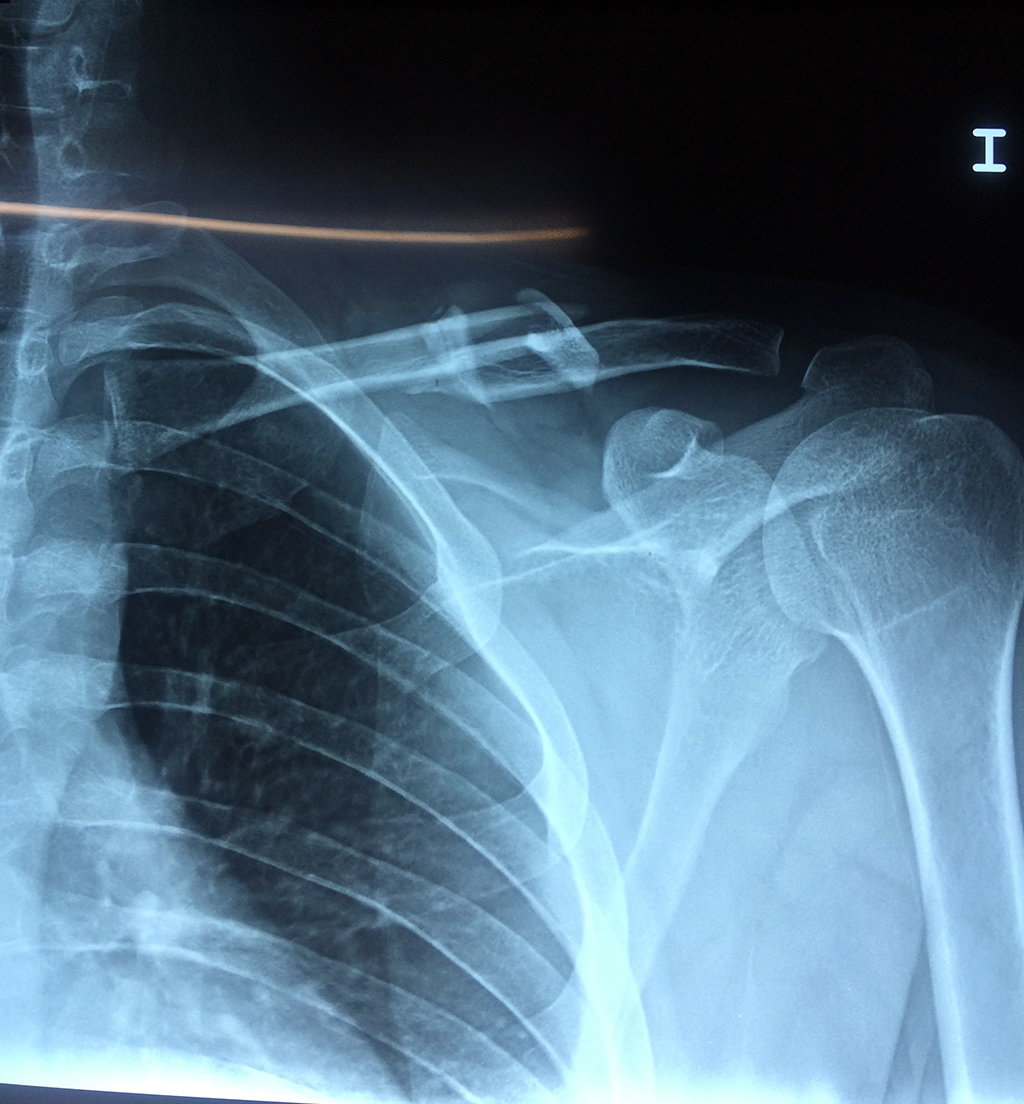

Cirugias en El Salvador - Clavícula

La clavícula es un hueso largo, con forma de "S" itálica, situado en la parte anterosuperior del tórax. Junto con la escápula forman la cintura escapular. Se puede palpar por toda su longitud y se extiende del esternón al acromion de la escápula, siguiendo una dirección oblicua lateral y posterior.

Se considera el único medio de unión entre el miembro superior y el tórax. A pesar de su aspecto, similar al de un hueso largo, posee una estructura semejante a la de un hueso plano, ya que carece de epífisis y de diáfisis, lo que la harían entrar dentro de la clasificación de hueso largo. Carece de un canal medular propiamente dicho.